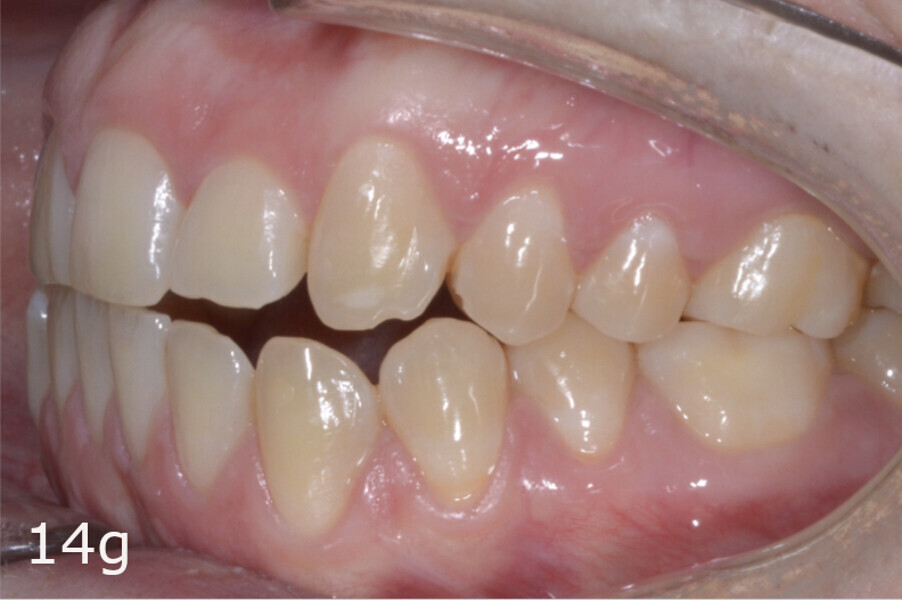

The total treatment time was 15 months. An Angle Class I relationship was established along with adequate anterior and canine guidance, establishing a functional occlusion. This not only ensures optimal masticatory function but also protects the teeth and the temporomandibular joint from excessive force. Maxillary and mandibular fixed retention were installed at the end of the treatment (Figs. 13–19).

This case report has shown that, with a comprehensive diagnosis, proper planning and patient compliance, aligners aided by elastics are an effective and efficient treatment alternative for correcting asymmetric Class III malocclusion. Aligners allow efficient distalisation in patients with anterior open bite or hyper-divergent patterns while minimising the risk of worsening the vertical problems.